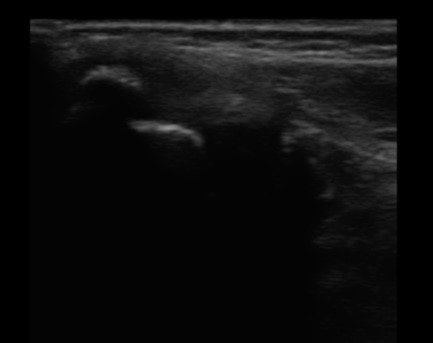

①しっかりとした画像検査

まず超音波エコーで画像診断を行い、炎症の程度、腫れの状態、疲労骨折を起こしていないかなどのチェックをしっかりと行い、練習を休まなければいけないのかなどの判断や改善までの治療計画を考えていきます。